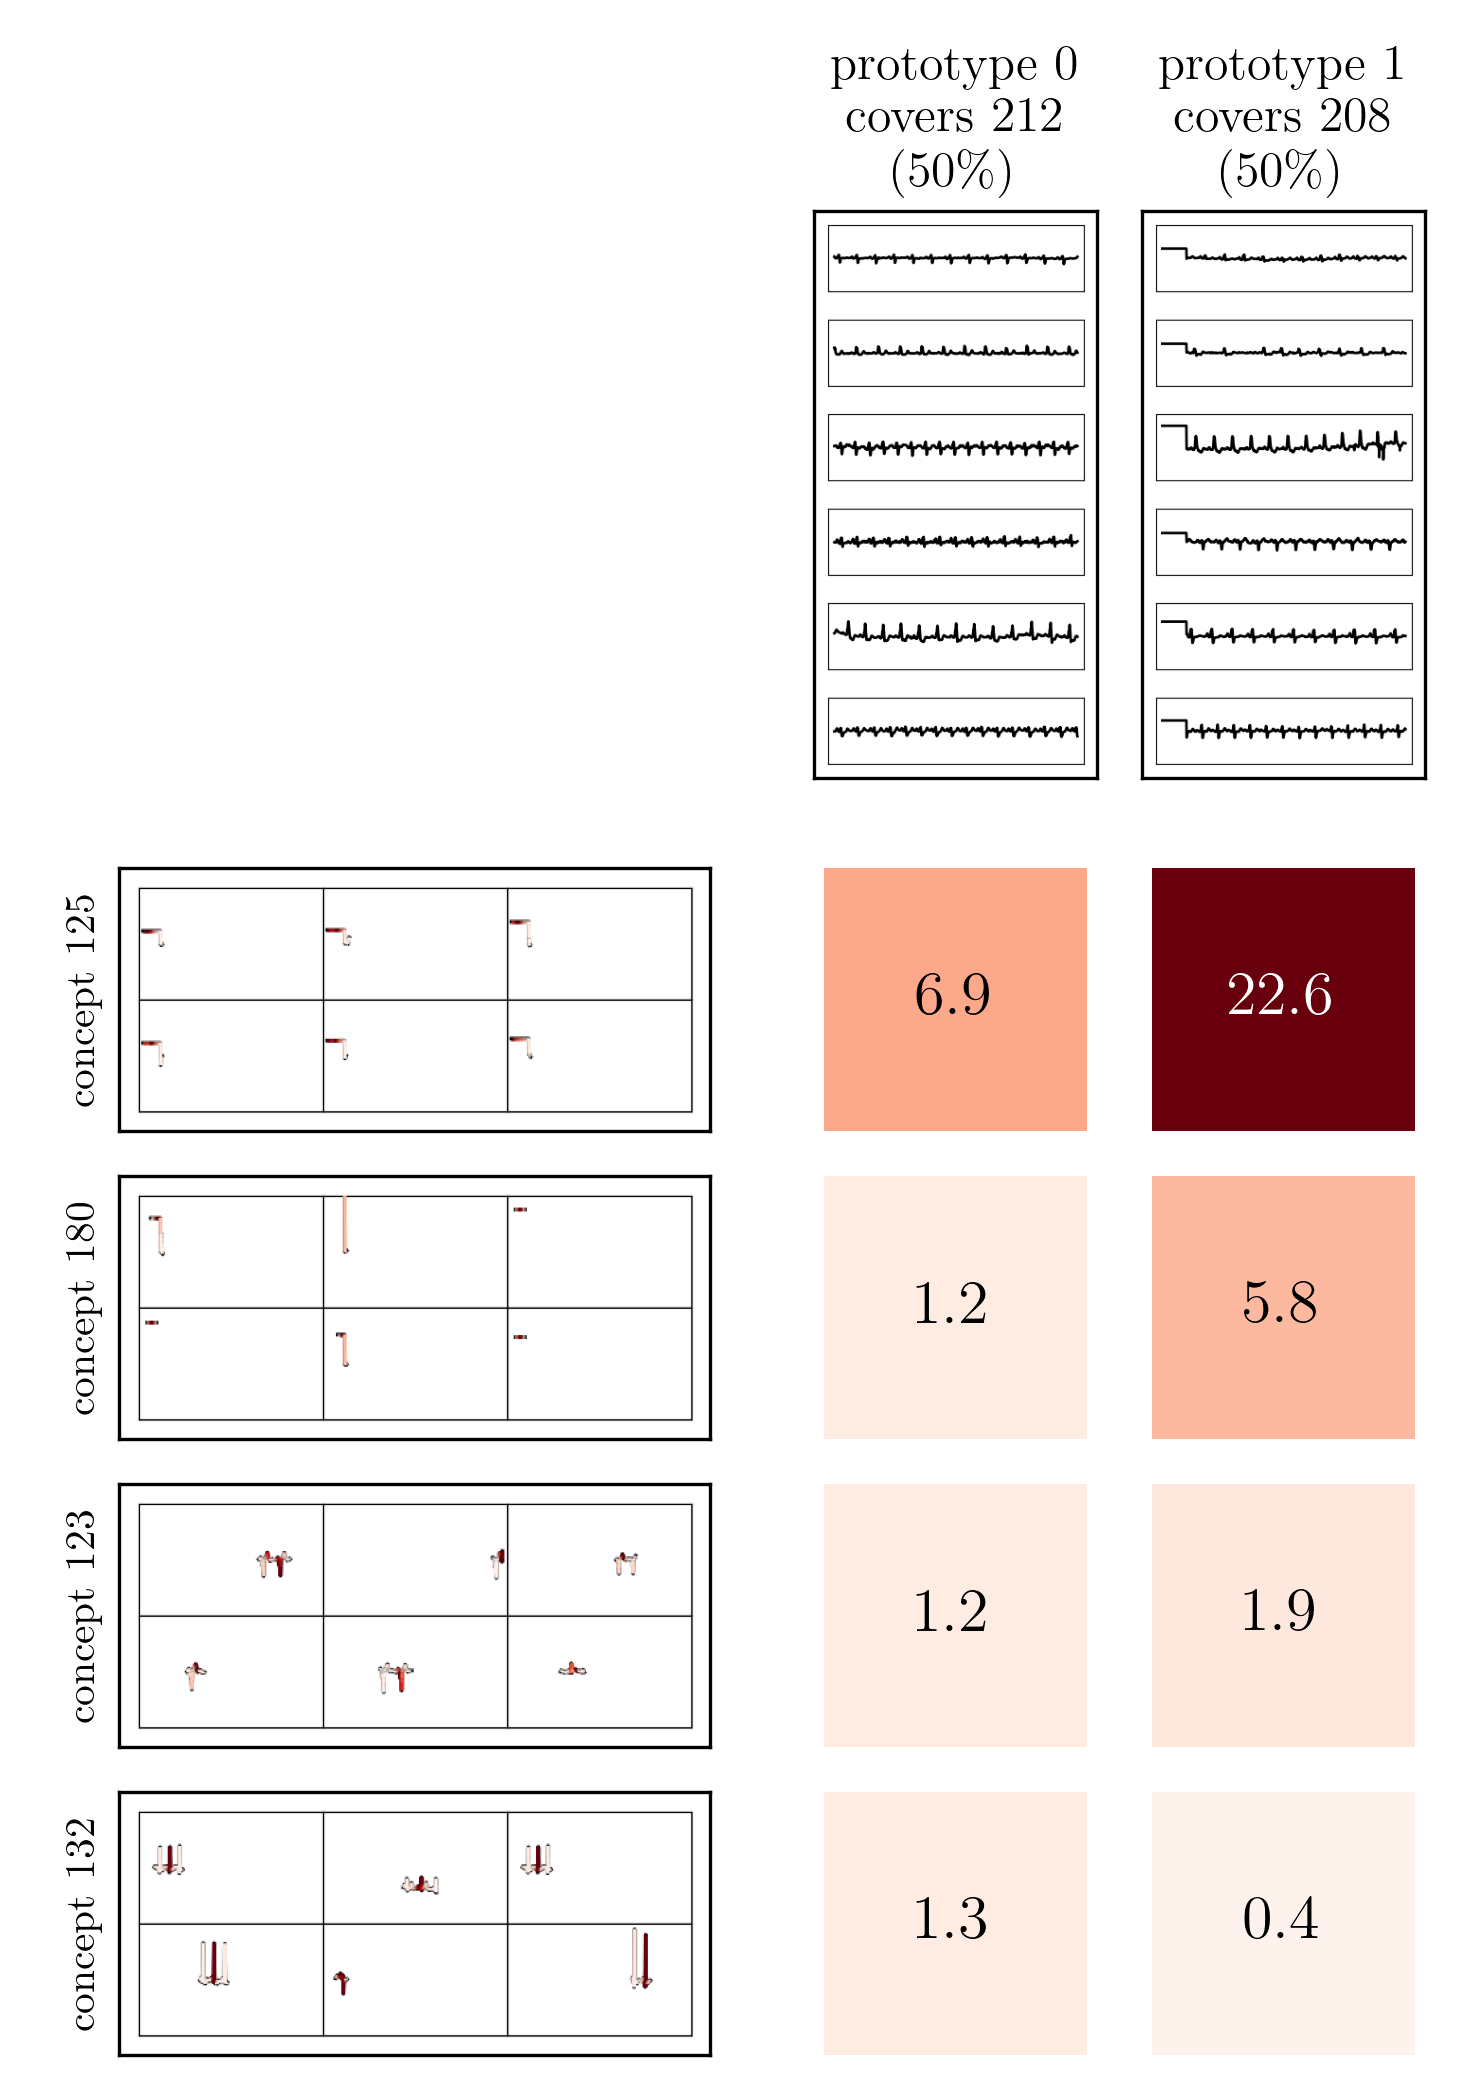

For example, Prototypical Concept-based eXplanations (PCX) [27] train Gaussian Mixture Models on max-pooled latent relevance scores and consider cluster means as stereotypical explanation, encoded as distribution over concepts (i.e., neurons).

Both input and latent relevance clustering require subsequent human supervision to determine whether outlier clusters represent valid or spurious behavior. To semi-automate this process, Anders et al. [3] propose using Fisher Discriminant Analysis [37] to rank class-wise clusterings by linear separability, while Dreyer et al. [27] computes similarities between prototypes. The results of clustering approaches can serve as an initial set for bias modeling methods outlined in Sec. 3.2, which can be refined iteratively. An example outlier cluster of latent relevances is shown in Fig. 4 (top), with all samples containing the spurious band-aid concept.

Data Perspective

We first apply SpRAy in input and latent space, computing input feature importance scores using LRP summed over color channels. To obtain latent relevances, we use intermediate relevance scores in the LRP computation process after the (out of four) residual block, max-pooling over spatial dimensions to yield relevance scores for layer with channels. The clustering of pairwise cosine distances between heatmaps is shown in Fig. 6 (top left). Detected outlier clusters contain samples with spatially coherent biases, e.g., the black circle around the lesions originating from microscopes (). In contrast, clustering latent relevance scores reveals more complex, less spatially dependent clusters, as shown in Fig. 6 (top right), including the ruler artifact () and the microscope (). Compared to those in input space, the cluster for the microscope in latent space represents a more diverse high-level concept. In the input space visualization, we further highlight samples from the ruler cluster detected in latent space. Instead of forming a cluster, they spread across the entire embedding space, indicating that the bias is too complex to be detected in input space.

Model Perspective

Next, we apply bias identification approaches from the model perspective by identifying outlier neurons based on activation pattern via DORA and relevance pattern by clustering pair-wise cosine distances between concept relevance scores. We focus on latent activations and relevances after the third residual block. DORA uses a distance function based on how neurons activate upon each others n-AMS, achieving high similarity when neurons activate upon similar input signal. A 2D visualization of the resulting distance matrix is shown in Fig. 6 (bottom left). Identified outlier concepts include ruler () and (white) hair (). We further compute pairwise cosine distances between latent relevance scores , aggregated over spatial dimensions, and apply UMAP to embed the resulting distance matrix in . This results in high similarity between neurons (concepts) that the model uses similarly for predictions. The concept clustering is visualized in Fig. 6 (bottom right), highlighting two outlier clusters focused on rulers () and blueish tint ().

Results for other classes, model architectures, and datasets are presented in Appendix A.6.1. This includes experiments with ECG data in Fig. 10, revealing the artificially inserted static noise in the attacked lead from both data and model perspectives. Notably, dominant spurious concepts, such as the artificial timestamp in HyperKvasir or the static noise in PTB-XL, may not be detected as outlier concepts. In such cases, analyzing prediction sub-strategies via PCX may provide additional insights on spurious inlier behavior. Hard-to-interpret concept representations pose another challenge for the model perspective. For example, the brightness artifact in CheXpert is not clearly visible in the concept UMAP (see. Fig. 15, right), but can easily be detected using SpRAy (Fig. 15, left) or PCX (Fig. 22). In summary, while all considered spurious features are detected, the choice of bias identification approach is crucial, as some shortcuts are easier to detect as outlier concept (e.g., ruler) and others via PCX (e.g., brightness, static noise in ECG).